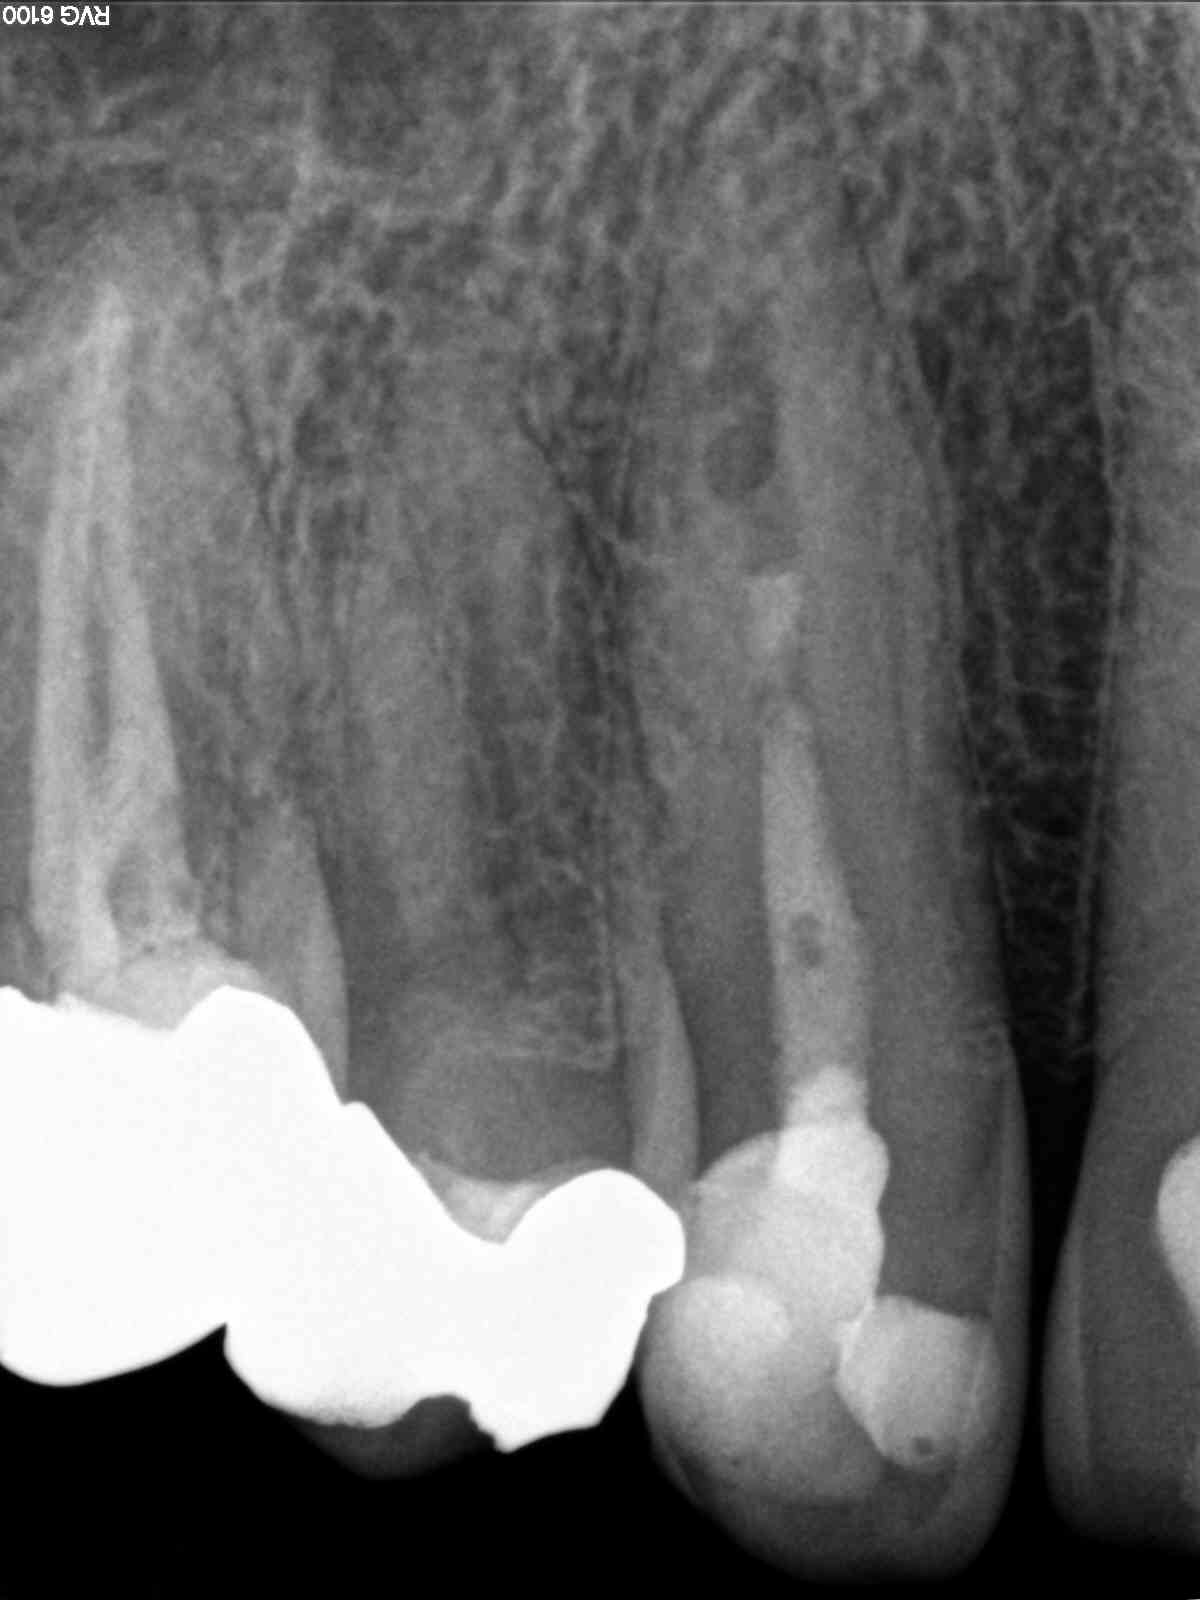

2D vs. 3D (XXVIII) – der Fallbericht